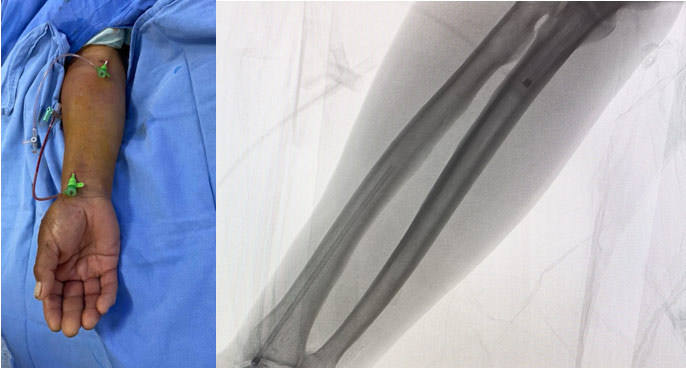

He was sent to the interventional cardiology department for primary angioplasty. Proximal right radial approach and 6 French introducer sheath were used.

The coronary angiogram revealed left system without lesions, ectatic RCA with acute total occlusion in the middle segment with grade 5 thrombus, and anomalous origin of the circumflex coronary artery arising from the proximal segment of the RCA with fusiform aneurysm in its middle portion (Figure 4 and Figure 5).